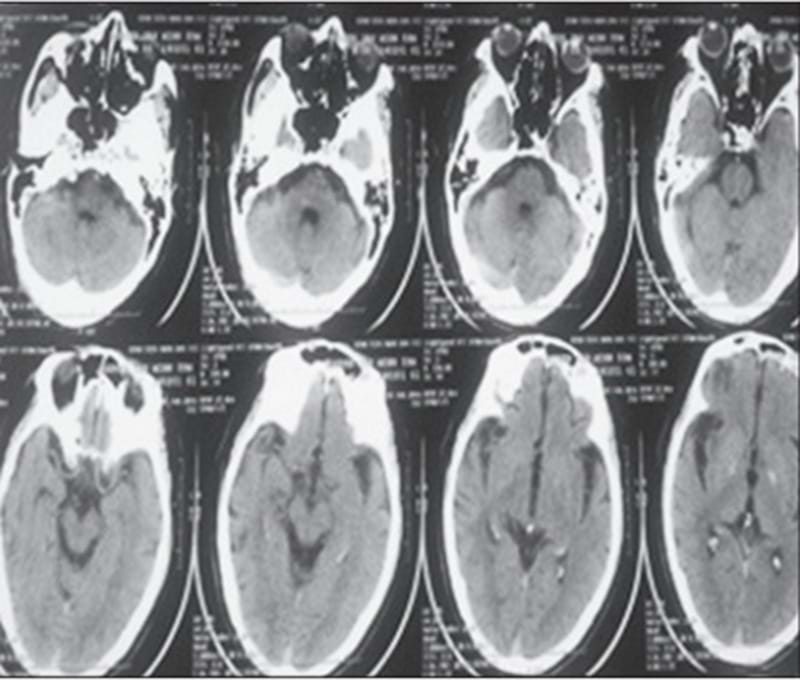

Điều trị bệnh nhân huyết khối tĩnh mạch não nghi ngờ dùng thuốc tránh thai lâu ngày. Ảnh: Minh Ngọc

Hình ảnh chụp MRI ở bệnh nhân huyết khối tĩnh mạch não. Ảnh: TL

Việc chẩn đoán sớm huyết khối tĩnh mạch não đôi khi rất khó khăn khi chỉ dựa trên triệu chứng lâm sàng vì bệnh có thể diễn biến từ từ và triệu chứng không đặc hiệu. “Tiêu chuẩn để chẩn đoán xác định huyết khối tĩnh mạch não là chụp cắt lớp vi tính (CT-scan) hoặc cộng hưởng từ (MRI) sọ não có tiêm thuốc cản quang/đối quang từ, với các chuỗi xung đặc biệt để khảo sát hệ thống tĩnh mạch não. Các phương pháp này giúp phát hiện cục máu đông và đánh giá mức độ ảnh hưởng lên nhu mô não”, BS. Hiếu chia sẻ.